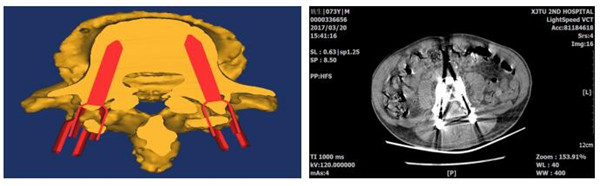

计算机3D模型导向模板(左图)及打印出的腰椎模型导板实物(右图)

术中运用3D打印导向模板辅助置钉

螺钉植入方向和长度与计划完全匹配